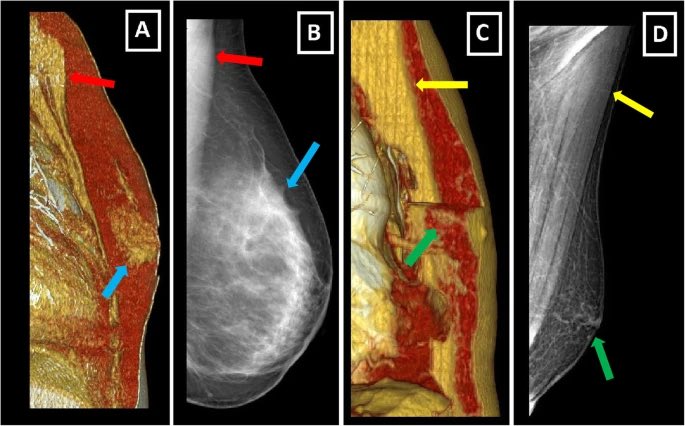

7️⃣وعادة بتم طلب فحص

١-الأشعه فوق الصوتية، لمعرفة نوع وصفات التورم او التغير

٢- احيانا يحتاج لعمل تصوير الثدي الشعاعي أو الماموغرام

في حال تبين ان الضخامة ليست نتيجة تثدي نحتاج لعمل

٣- خزعة، يتم فيها ادخال ابرة للثدي وشفط عدد من الخلايا للفحص في مختبر بالميكروسكوب